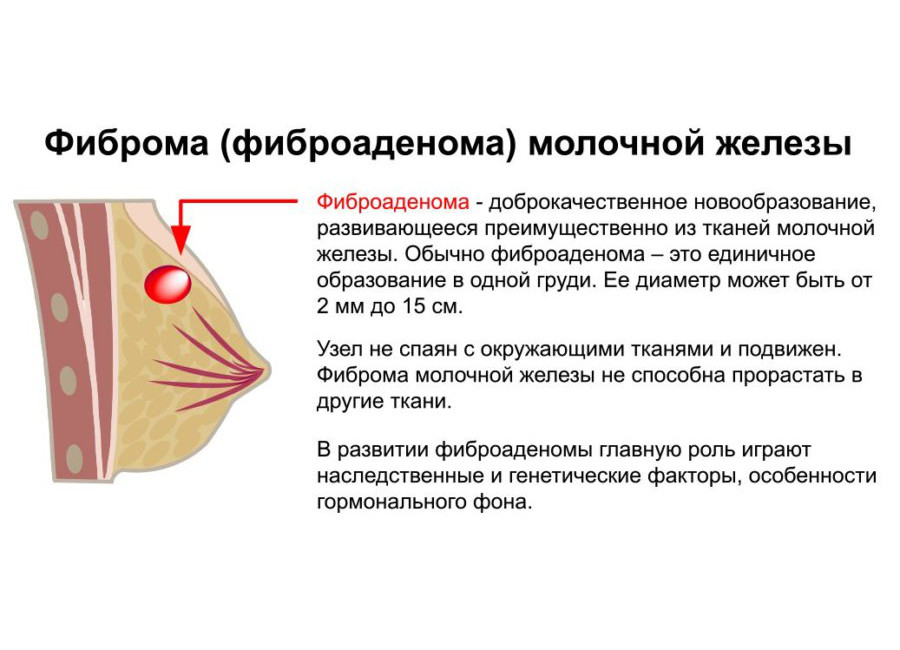

Уплотнения в груди могут быть вызваны различными причинами, включая кисты, фиброаденомы или инфекционные процессы. Важно понимать, как правильно подходить к их лечению и когда обращаться к врачу. Следующие советы помогут вам разобраться в этом вопросе и обеспечить здоровье своей груди.